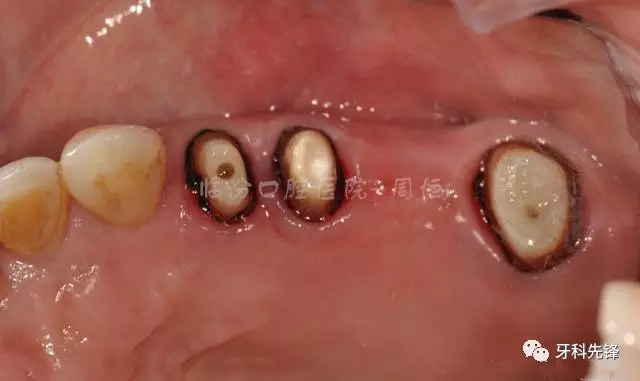

圖4 拆除原修復體牙列照

640.webp (5).jpg

圖9去除腐質(zhì)口內(nèi)照

640.webp (13).jpg